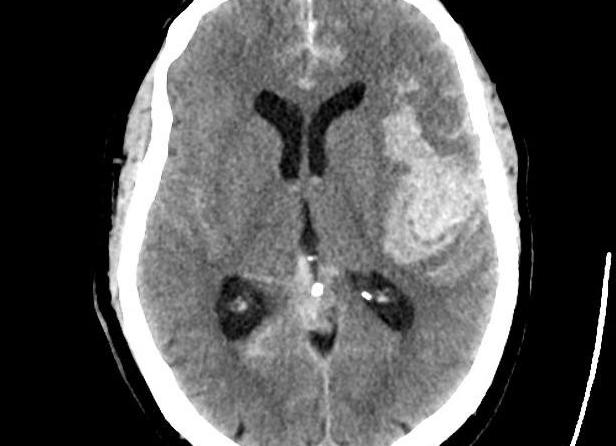

В основе работы томографа лежит рентгеновское излучение. С помощью рентгеновских лучей создаются черно-белые изображения органа под различными углами. Обработав полученные со сканера данные, компьютер выдает трехмерное изображение участка или всего головного мозга. Объемная проекция позволяет выявить ушибы, инсультные повреждения и другие нарушения целостности тканей мозга.

Для выявления онкологических очагов и труднодиагностируемых патологий при компьютерном сканировании может применяться контрастное вещество. Исследование мозга с контрастом носит название «ангиография». Контрастный маркер, накапливаясь в пораженных тканях, делает визуализацию патологического участка более четкой. На снимках отчетливо видны границы поврежденных тканей и структур.

На мониторе после цифровой обработки врачи получают послойное трехмерное изображение мозга, где можно рассмотреть патологические очаги: опухоли, травмы, кисты, абсцессы, кровоизлияние.

Исследование на компьютерной томографии дает черно-белые послойные снимки органа. Снимок КТ головного мозга получается в трех проекциях: фронтальной, аксиальной и сагиттальной. На картине изображен мозг и его сосуды. Врач изучает пространственное расположение всех структур относительно друг друга и наличие патологических очагов.

Расшифровка КТ – это сравнение нормы и патологии. Диагност оценивает контуры мозга, светлые и темные области, патологические тени, инородные тела. Наличие новообразований оценивается по косвенным и достоверным признакам. Например, достоверный признак – смещение структур мозга. Гиподенсные очаги головного мозга на КТ – это косвенный признак опухоли.